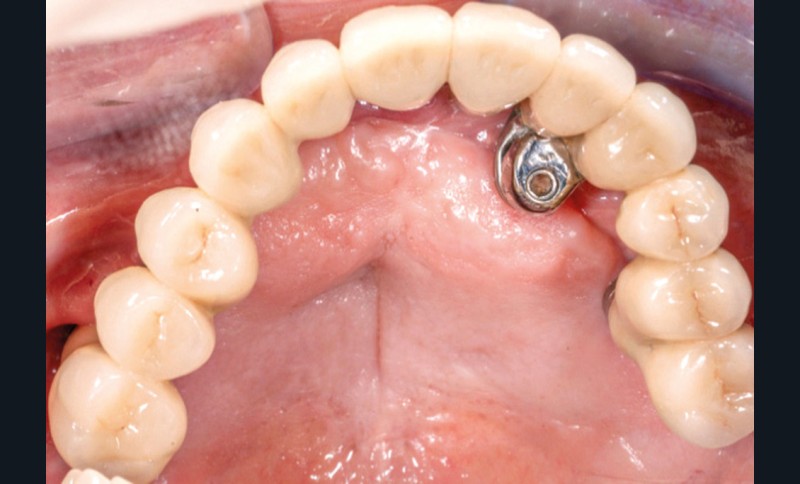

Dans le cas clinique présenté dans cet article, le patient édenté total bimaxillaire se plaint d’une gêne importante et d’une insatisfaction de son sourire en lien avec un plan d’occlusion prothétique inadapté (fig. 1 et 2).